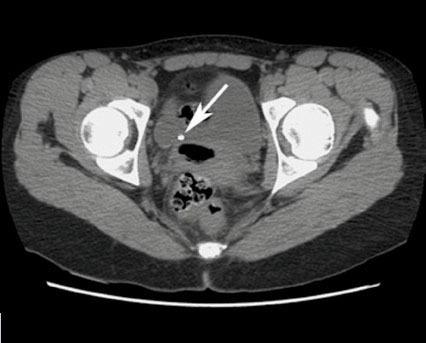

Vladimir Gomola, Jacques Hubert (La Revue du Praticien) Tomodensitométrie non injectée en coupe axiale montrant une lithiase du bas uretère droit au niveau de la jonction vésico-urétérale.